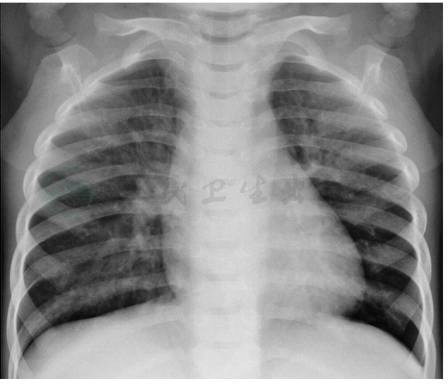

(一)X线检查

胸部X线片(图1)是本病的主要诊断手段。胸部X线片显示患肺或肺段透光度增加,肺野和肺门偏小,肺纹理稀疏、纤细,有不同程度的支气管扩张。重症患者纵隔向患侧移位。

图1单侧透明肺的胸部X线片